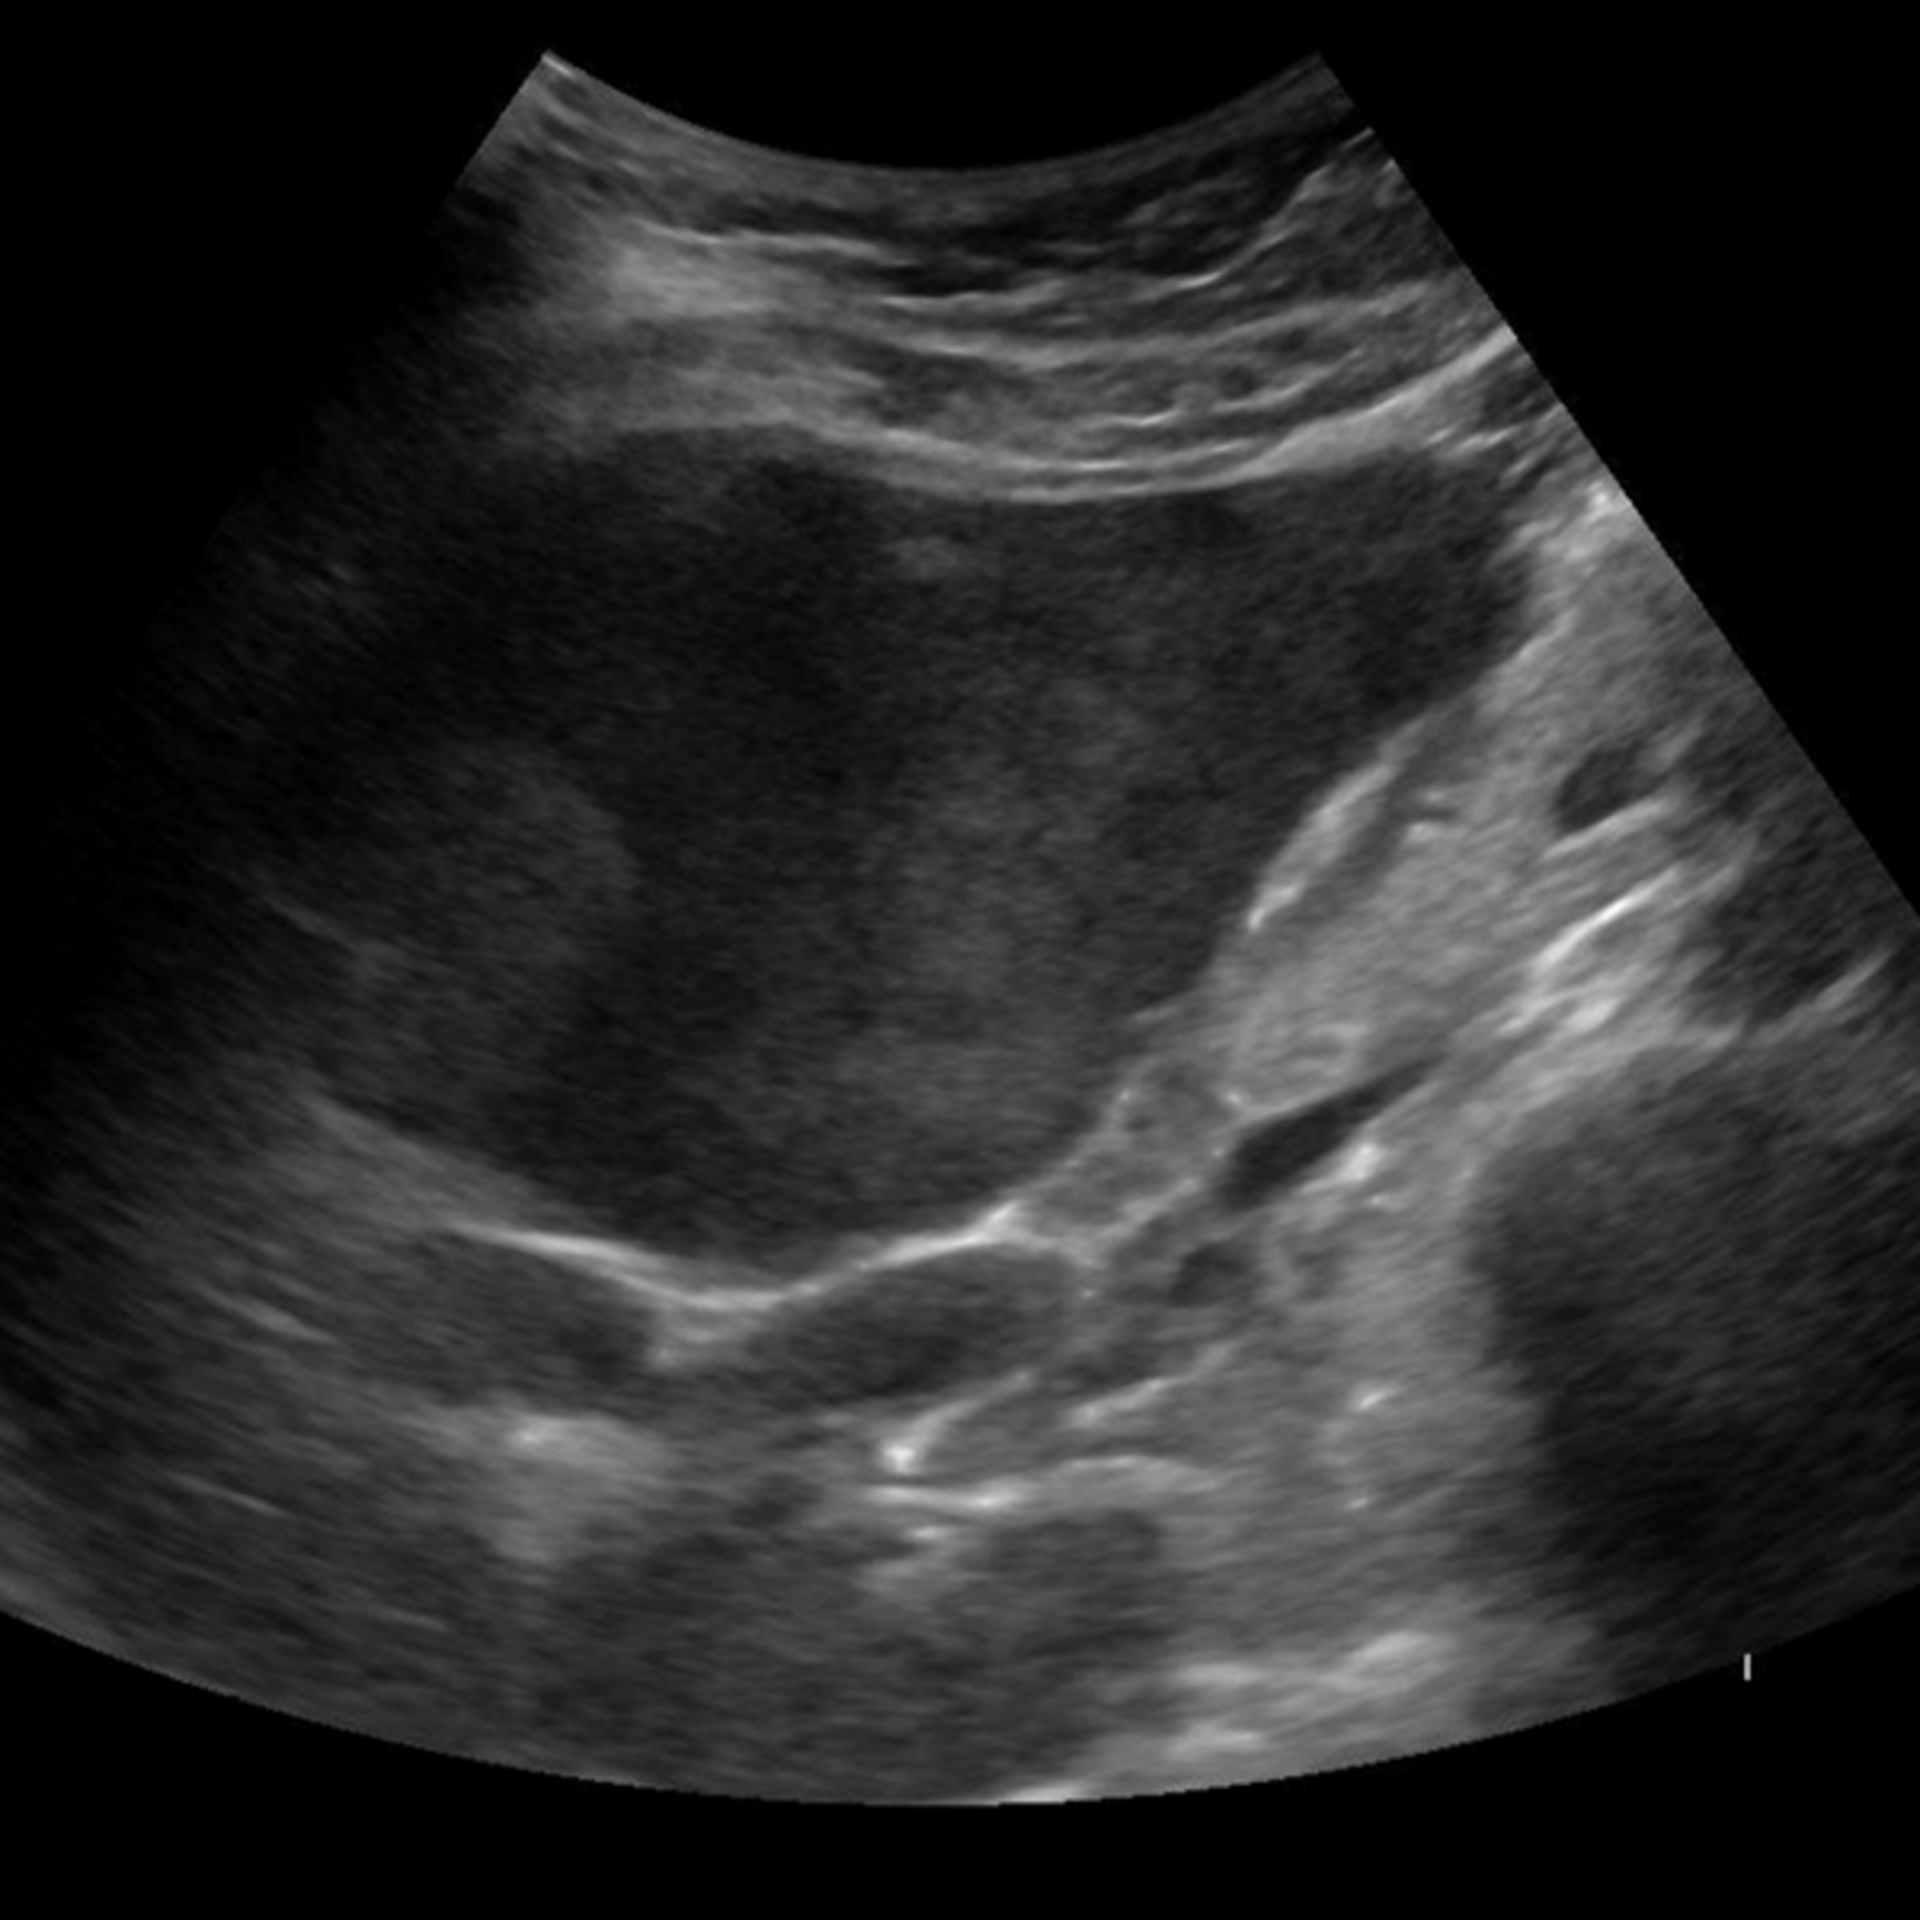

SmartLiva ทำงานเหมือน “อัปเกรด” จากภาพอัลตราซาวด์ขาวดำธรรมดาให้กลายเป็นผลวินิจฉัยที่อ่านง่ายและแม่นยำ โดยอัปโหลดภาพผ่านเว็บได้ทั้งบนคอมพิวเตอร์หรือแท็บเล็ต จากนั้นระบบจะช่วยปรับภาพให้ชัดขึ้น คัดเฉพาะบริเวณเนื้อตับที่ต้องวิเคราะห์ และทำให้ภาพดูเข้าใจง่ายขึ้นด้วยการไฮไลต์เป็นสี (เช่น ตับเป็นสีแดง ไขมันเป็นสีเหลือง) เพื่อให้เห็นความผิดปกติได้ทันที โดย AI จะทำการประเมิน 3 เรื่องพร้อมกัน คือ ประเมินระดับพังผืด/ความแข็งของตับ (F0–F4), ตรวจหาความผิดปกติของเนื้อเยื่ออย่างถุงน้ำหรือมะเร็งตับ และตรวจหาพยาธิใบไม้ตับ ซึ่งตัว AI จะทำการประมวล วิเคราะห์ และสรุปผลออกมาเป็นรายงานพร้อมภาพประกอบและคำอธิบายที่คนทั่วไปเข้าใจได้